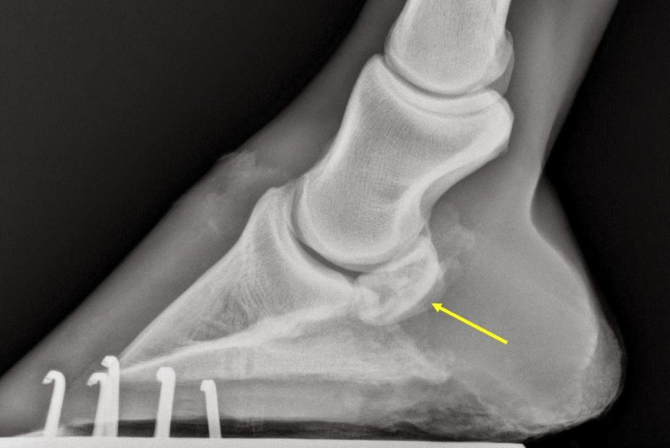

Na avaliação radiográfica, devido à localização e ao formato complexo do osso navicular, é necessário realizar, no mínimo, três projeções distintas para uma análise completa.

• Dorsoproximais-palmarodistais anguladas

• lateromedial

• Palmaroproximal-palmarodistal oblíqua

Fig 2 - Alterações radiográficas observadas na degeneração do navicular. Projeção dorsoproximal-palmarodistal em ângulo de 65 graus: A, normal; B, entesófito na extremidade e borda proximal irregular; C, invaginações em formato de pirulito na borda distal; D, formação de lesão cística. Projeção lateromedial: A, normal; B, perfil alongado do navicular causado pelo remodelamento (formação de entesófito); C, erosão do córtex flexor; D, formação de lesão cística. Projeção palmaroproximal-palmarodistal: A, normal; 13 B, erosões do córtex flexor; C, aumento de volume da fossa e erosões do córtex flexor; D, formação de lesão cística (THRALL, 2010).